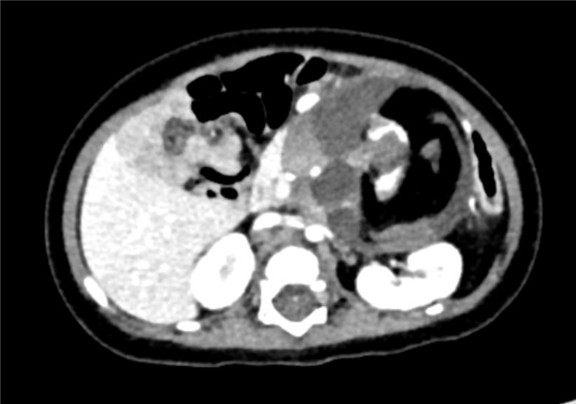

现病史:患儿于孕期26周体检时发现腹部囊实性肿块,大小约2.4*2.2cm,出生后密切关注患儿腹部情况,因腹部肿块逐渐增大于2017-08-10来我院门诊就诊,行腹部CT平扫检查发现胰腺下方见团块状低密度影,其内密度不均,可见脂肪密度影及钙质密度影,大小约8cm×5cm。出生后患儿无反酸、厌食、恶心、呕吐,无腹痛、腹泻、便秘等不适症状,今为行手术治疗来我院。

下腹部增强CT示:腹腔巨大占位,考虑畸胎瘤可能性大

术前CT检查:

动脉期

静脉期

平衡期